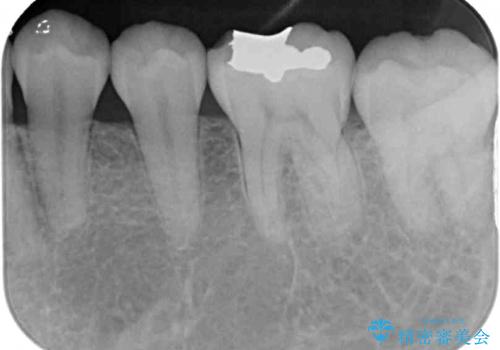

- 左下の奥歯が、冷たいものを食べるとしみて、舌で触るとザラザラすることが気になり来院された患者様です。

以前他院で治療したCR(樹脂の材料)が劣化し、その隙間から冷たいものがしみている可能性が高いことがわかりました。

嚙み合わせの力が強いため、再びCRやセラミックインレーによる修復を行っても割れてしまう可能性が高いので、

ゴールドインレーによる修復を行うこととしました。